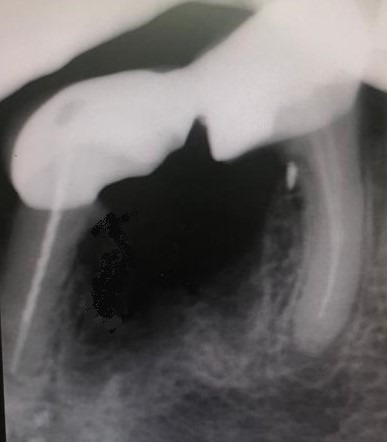

Esto provocaba en la paciente un gran dolor, pero ella no contemplaba en ese momento la opción de levantar la prótesis para explorar las piezas que había debajo, poder visualizar la destrucción dental y rehacer todo con una prótesis nueva. Por tanto, para quitar el dolor normalmente habría que haber hecho las extracciones de los dos molares, lo cual sería muy invalidante. En la clínica decidimos hacer una endodoncia de la raíz distal del último molar a través de la prótesis por la zona oclusal, y hacer odontosecciones de las raíces lesionadas sin quitar la prótesis. Ésta va permanecer tal como estaba.

Lo cierto es que las raíces  ya estaban bastante separadas de el resto de los molares correspondientes por su destrucción, lo que nos permitió la extracción de estas raíces en concreto. Teniendo en cuenta también que las raíces mesial y distal de cada molar no estaban unidas entre sí, sino que había una separación entre ellas.

La técnica quirúrgica para este menester es parecida a una apicectomía, pero en lugar de quitar solo el ápice radicular quitamos toda la raíz dental. Así pues lo que se hizo fue extracción de la raíz distal del primer molar y extracción de la raíz mesial del segundo molar. Con lo que la prótesis sigue teniendo dos pilares.